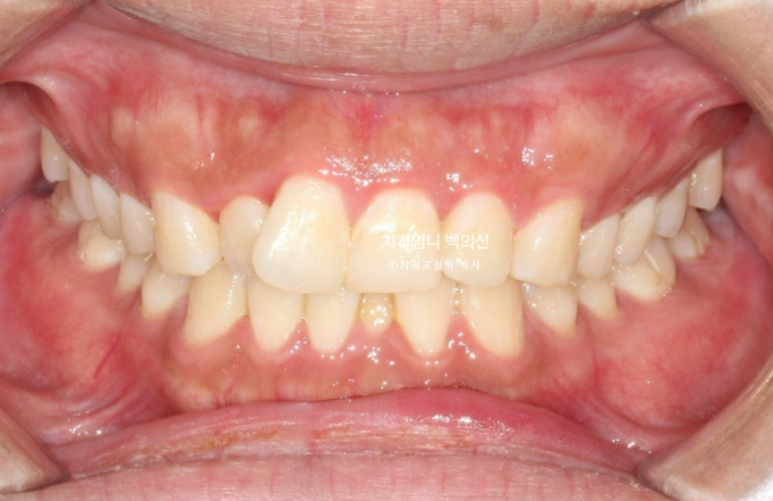

25년 2월 교정상담을 위해 오신 분입니다.

25.02

앞니가 기울어져 있고 중심선이 안 맞습니다.

어금니교합은 좋은 편입니다.

어금니 배열도 좋은 편이라 앞니 부분교정 권유드렸습니다.